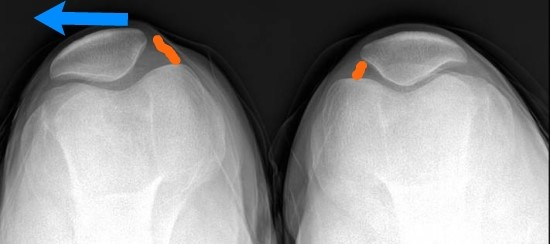

슬개대퇴 통증 증후군이란 무릎 앞쪽에 있는 뼈인 슬개골과 허벅지뼈인 대퇴골이 제대로 맞물리지 않아 발생하는 전방 슬관절 통증(슬개골 후방 통증)입니다. 진단을 내리기가 어렵고 애매모호하지만 전체 무릎관절 질환의 25% 이상을 차지할 만큼 흔한 질환이지요.

슬개대퇴 통증 증후군의 원인으로는 대퇴사두근 근력의 약화 또는 힘줄의 염증, 연골연화증이나 해부학적 모양의 이상 같은 슬개골 자체의 문제, 무릎 지방패드의 염증, 내측반월판의 병변 등 여러 가지가 있습니다. 저는 무릎을 굽히고 펼 때마다 슬개골이 바깥쪽으로 살짝 빠졌다 들어오는 슬개골 아탈구가 있습니다. 해부학적 구조는 괜찮은 것 같은데, 아마도 지나치게 운동을 안 해서 초래된 대퇴사두근 근력 부족에 의한 것으로 생각됩니다.